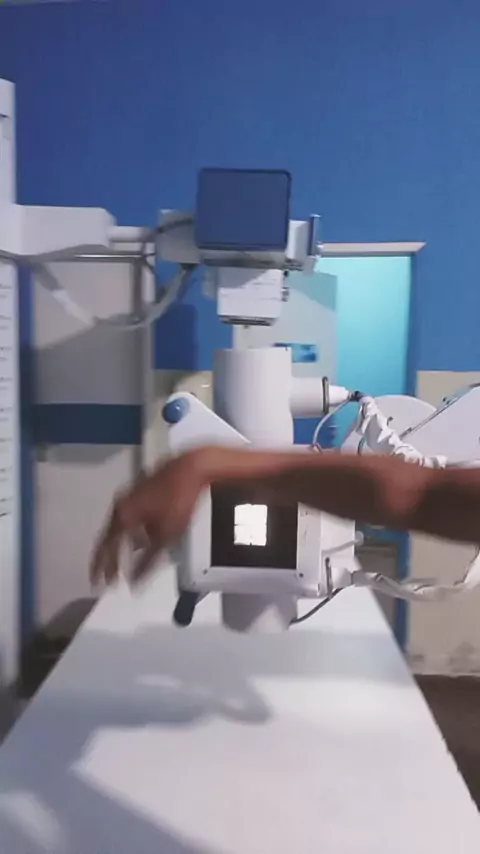

Sala de RX parte 1 #ultra10kvis #5AnosDeGabigol #leiaNokwai #EstrelaDeFamília

Hoje estou de plantão no RX #EstrelaDeFamília #ultra10kvis #vida